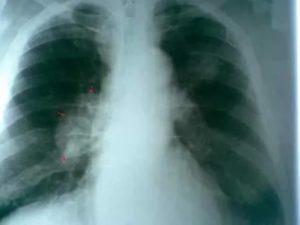

Увеличенные лимфоузлы очень часто встречаются в корне легких, это самая распространенная патология, вызываемая туберкулезным бронхоаденитом, раком. В группу риска попадают заядлые курильщики. Также патология выявляется при переохлаждении и после длительного острого вирусного заболевания, сопровождающегося снижением иммунитета (например, бронхопневмония).

Раковое заболевание проявляется в форме образования злокачественных опухолей, метастазы могут поразить абсолютно любой орган. Рак легких в 95% случаях поражает плевру и вспомогательные ткани, такие как лимфоузлы. Именно это заболевание чаще всего приводит к летальному исходу.

В первой стадии лимфатические узлы «не участвуют».

Увеличенные лимфоузлы легких на рентгене видны, когда болезнь переходит во вторую фазу, сначала «под удар» попадают бронхиальные, а на третьей стадии средостенные, бронхолегочные и надключичные узлы.